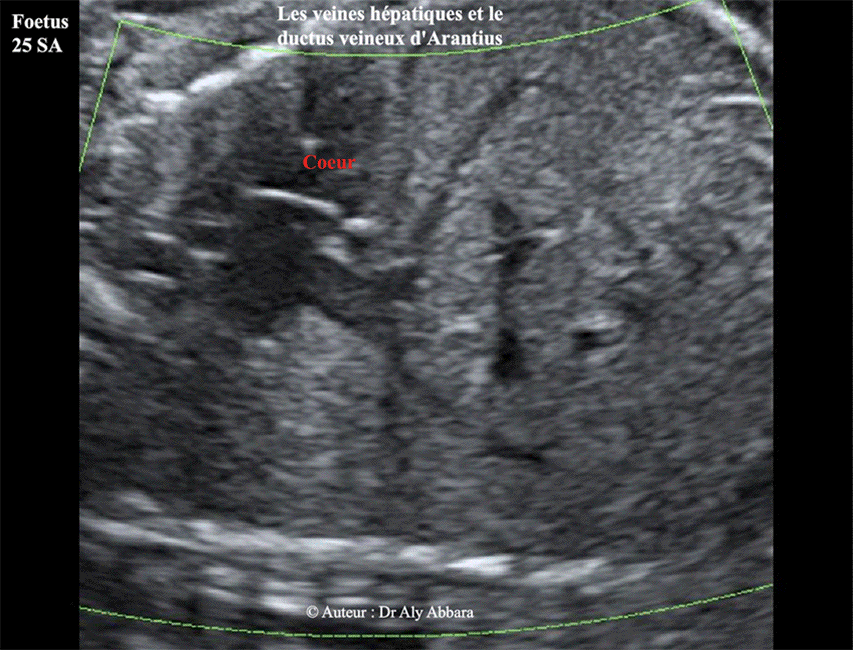

Images échographiques montrant les trois veines hépatiques et leurs rapports anatomiques avec le ductus veineux (canal veineux), branche de la veine ombilicale gauche.

Sur cette image on peut remarquer que le ductus veineux est plus proche des veines hépatiques, gauche et intermédiaire (qui sortent du foie du même site) que la veine hépatique droite qui sort du foie d'un site un peu plus à droite que le site précédent.

Fœtus âgé de 25 SA dans le cas présent.